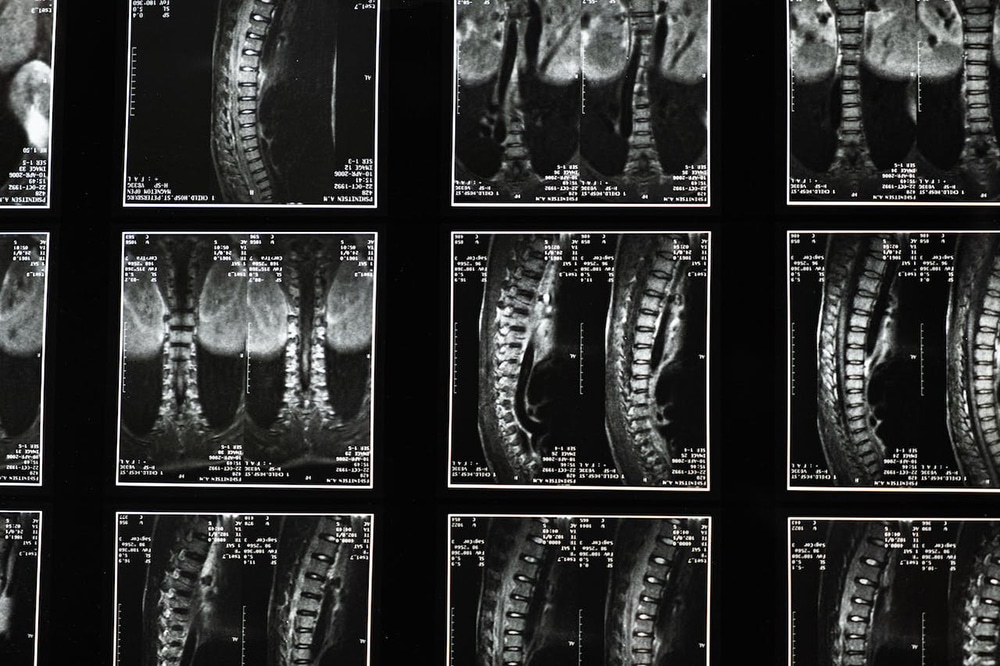

What Is a Spinal Cord Injury?

A spinal cord injury refers to any physical damage that occurs to the spinal cord. An SCI can result from direct physical trauma to the spinal cord itself or from damage to the surrounding nerves and bones, and because the spinal cord is involved in so many different functions and in so many different areas of the body, the symptoms of an SCI can vary widely.

Where the spinal cord is damaged, and the extent of that damage are major factors in the severity of the injury. The higher the injury site is on the body, the more areas of the body are affected, and any areas of the body below the injury site will be impacted by the damage.